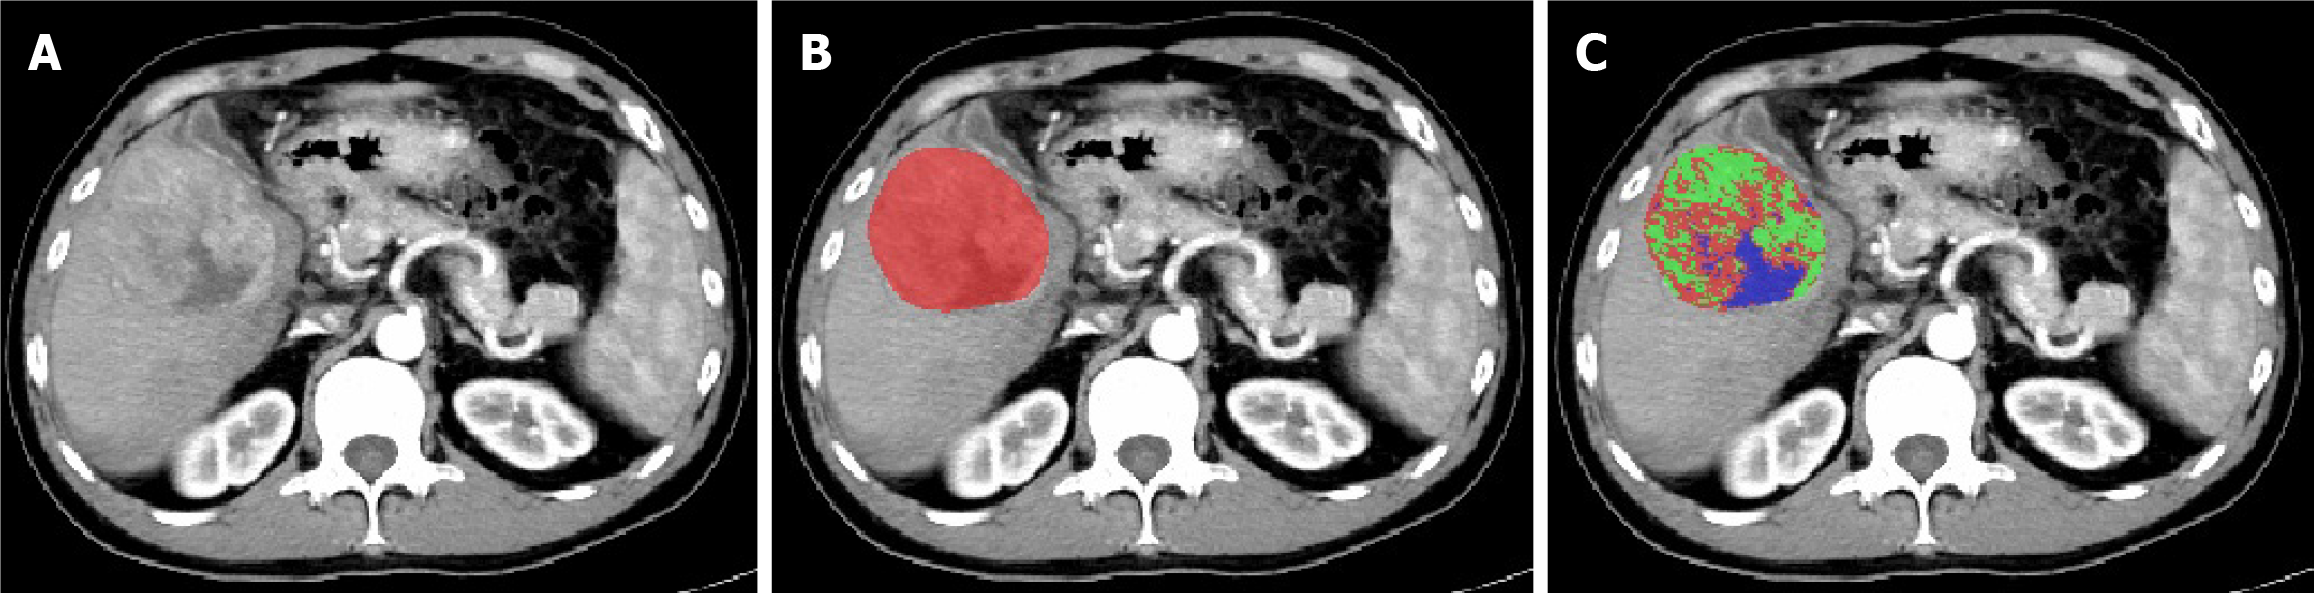

Download all patients' liver CT-enhanced arterial phase images in transverse DICOM format and convert them to NIFTI format for storage. Preprocessing of CT image datasets: First, calibrate the voxel spacing of all images to 1 mm × 1 mm × 1 mm. Then, standardize the window width and window level to 259 HU and 40 HU, respectively. Using ITK-SNAP 3.8.0 software, a radiologist with over 10 years of experience independently performed manual slice-by-slice segmentation of tumor regions in the CT arterial phase images (Figure 1). These segmentations were then cross-checked one-by-one by a senior-level physician (the study workflow is illustrated in Figure 2).